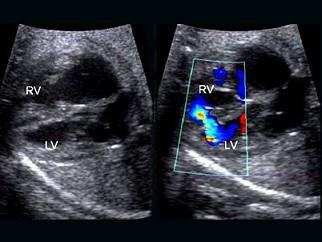

问题 女,6岁。门诊体检时发现心脏杂音,经超声心动图检查,如图所示,诊断为先天性心脏病(室间隔缺损肺动脉高压)。下列哪一项不符合此病的体检所见 ( )

选项 A、剧烈哭闹后出现发绀 B、胸骨左缘第3~4肋间触及收缩期震颤 C、胸骨左缘第3~4肋间闻及Ⅲ级全收缩期杂音 D、心尖部可闻及舒张期杂音 E、肺动脉瓣区第2音减弱伴固定分裂

答案 E